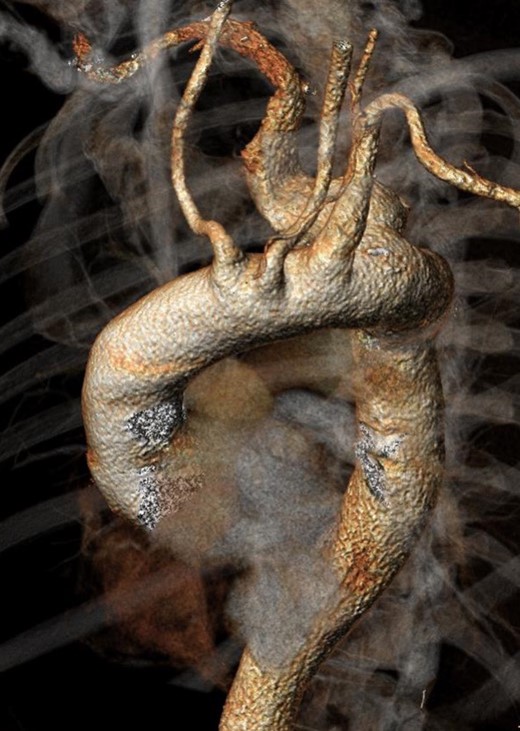

Twenty-two months after the procedure, the patient referred to our Unit due to the worsening of dysphagia. A new CT scan showed the enlargement of the aneurysmal sac (115 mm) due to the persistent Type II endoleak from bronchial arteries (Fig. 3). An endovascular embolization of the target vessels was not feasible due to the impossibility to cannulate the bronchial arteries without direct puncture. A preoperative esophageal endoscopy was performed to exclude the presence of esophageal–aneurysmal fistulas and an open repair with right thoracotomy and aneurysmorraphy of the AARSA was performed to occlude the bronchial side branches and to reduce the compression of the giant aneurysm on the esophagus (Fig. 4, 5). The postoperative course was uneventful and the patient was discharged on the 11th postoperative day.

Intraoperative image showing the opened sac with the back bleeding from bronchial vessels.

Only two papers [4, 5] previously reported the treatment strategies for Type II endoleak following endovascular or hybrid AARSA repair. In one case, a Type II endoleak from bronchial arteries in an aberrant left subclavian artery aneurysm, previously treated by thoracic endoprosthesis implant, was fixed by endovascular means with coils implanted through a gap between the prosthesis and the subclavian artery. In the other case, such a complication, developed after hybrid repair of AARSA, was treated with aneurysmal sac wrapping and ligation of the patent collateral arteries. In our case, there was no option to gain further access to the aneurysmal sac by endovascular means, so an open approach was mandatory (Fig. 5).

Intraoperative image after intra-sac arterial suture; the endograft is well visible on the bottom.